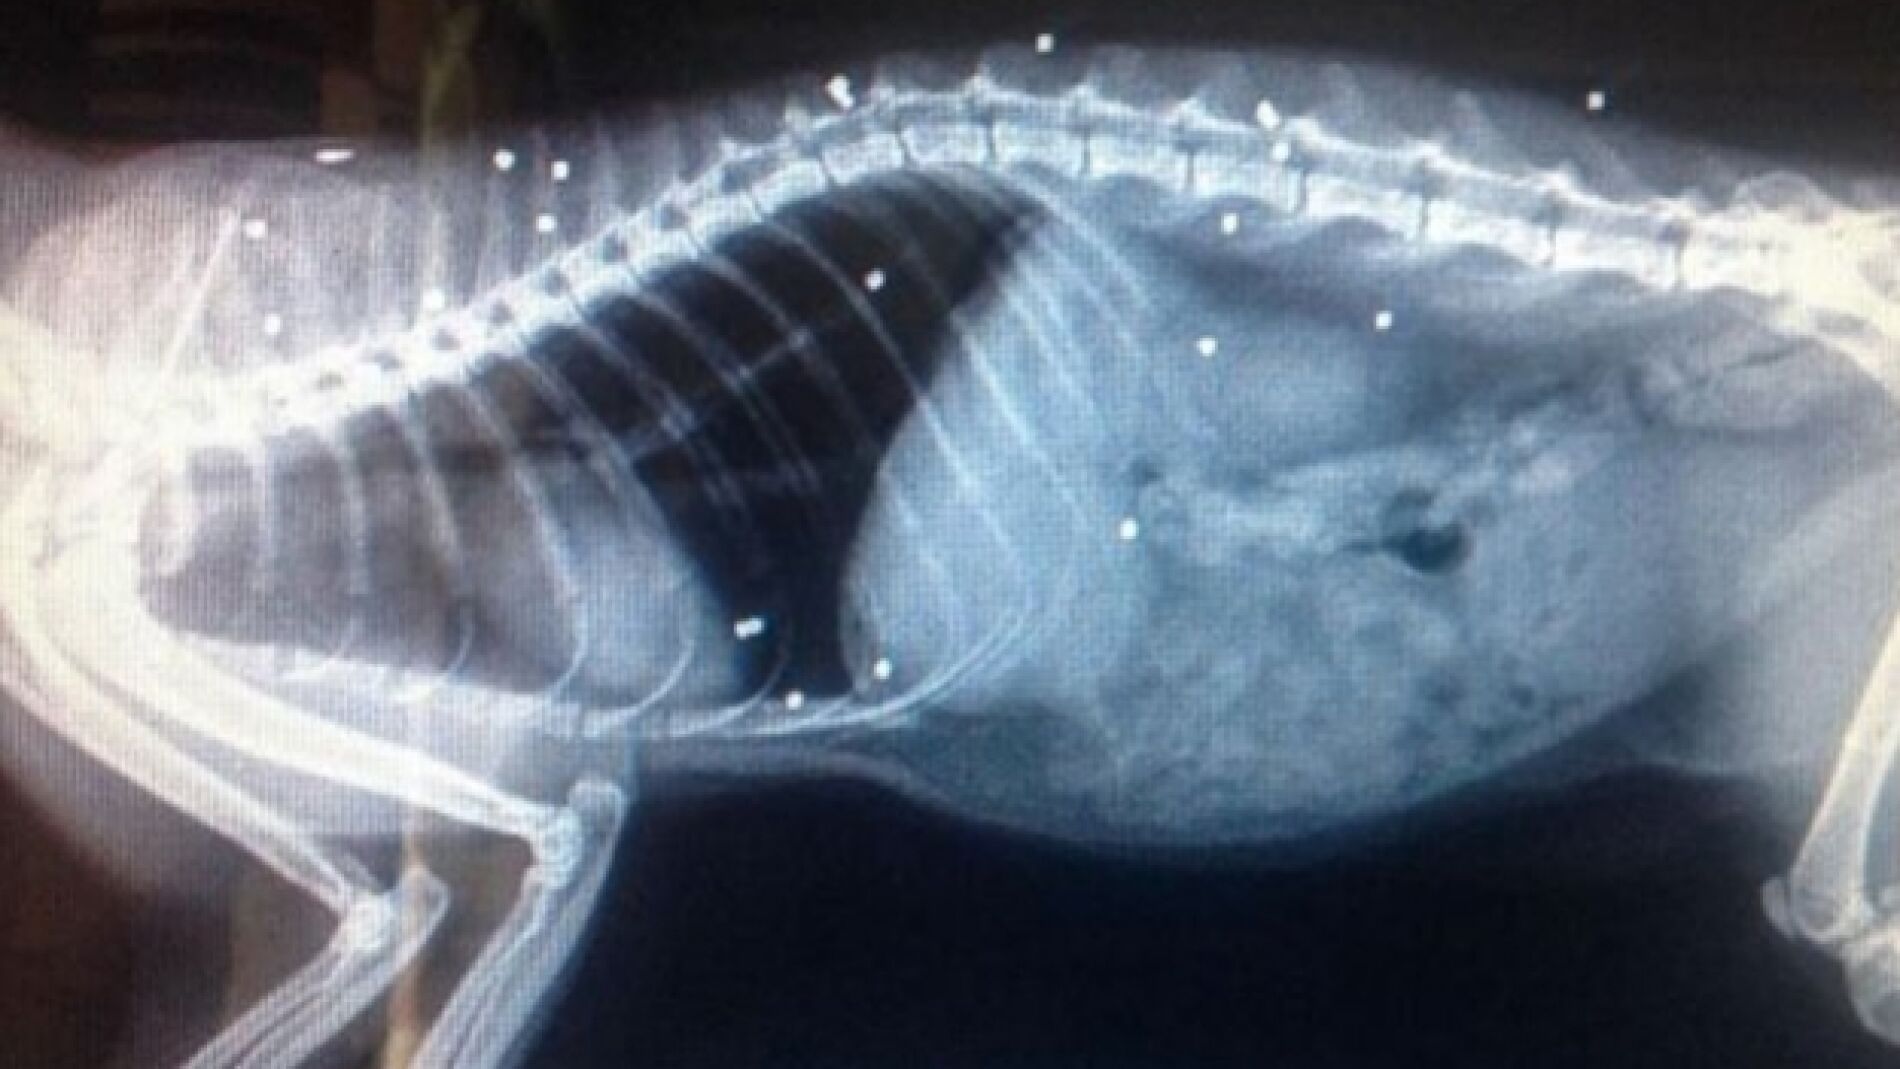

Fue llevado a un veterinario donde fue examinado con rayos X. La radiografía reveló que su cuerpo estaba repleto de perdigones.

Por su parte, el veterinario ha señadado que otras dos balas impactaron en su médula espinal dañándola de forma seria, y que por tanto, "es un milagro que haya sobrevivido".